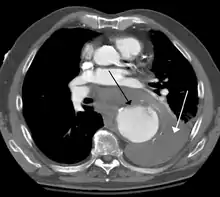

Diagnosis

Thoracic aortic aneurysm is defined as a cross-sectional diameter exceeding the following cutoff:

A diameter of 3.5 cm is generally considered dilated.[5] However, average values vary with age and size of the reference population, as well as different segments of the aorta.

The size cut off for aortic aneurysm is crucial to its treatment. A thoracic aorta greater than 4.5 cm is generally defined as aneurysmal, while a size greater than 6 cm is the distinction for treatment, which can be either endovascular or surgical, with the former reserved for pathology at the descending aorta.[10]